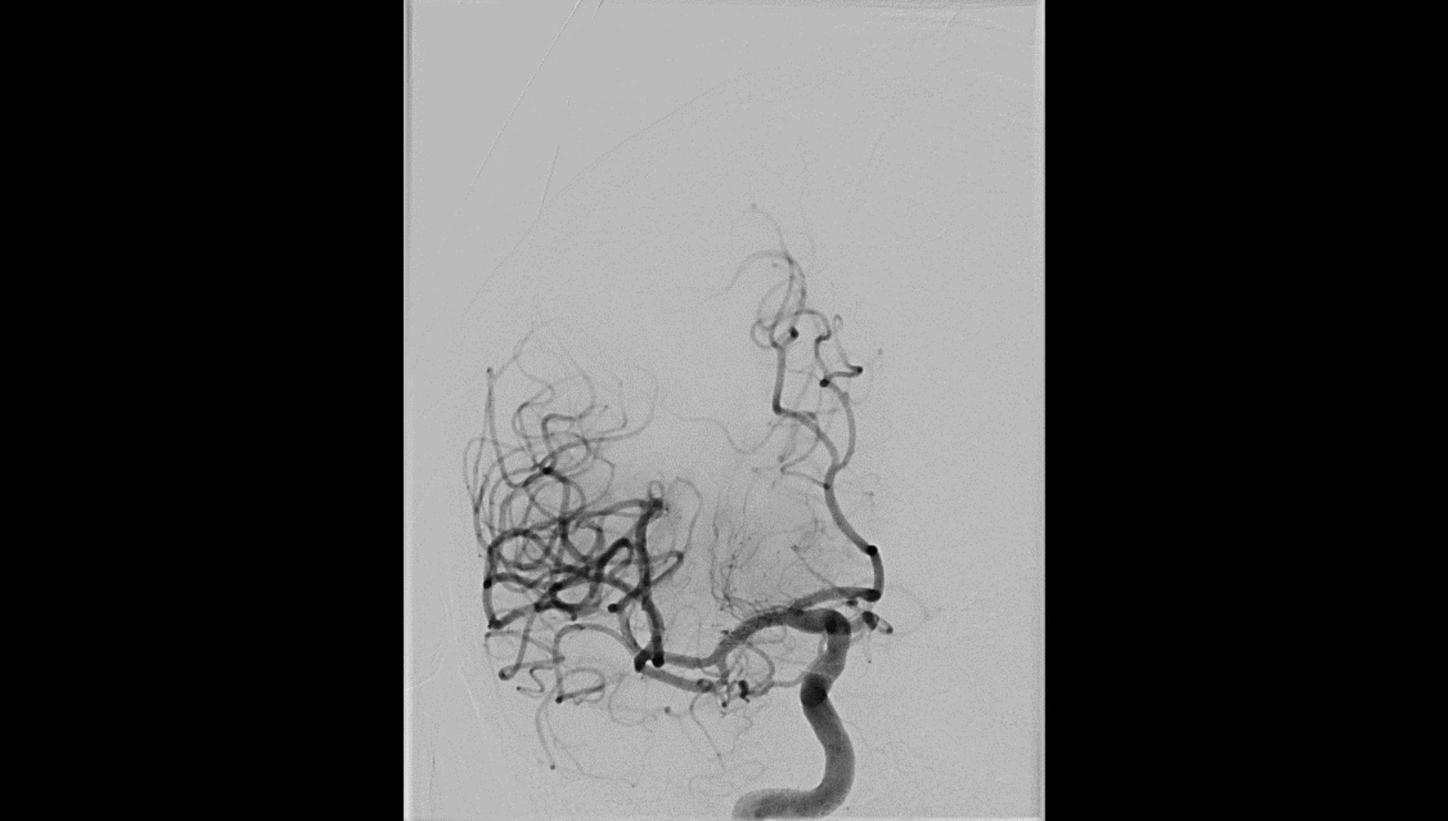

AP projection

Lateral projectionFollow-up DSA to visualize treatment success

Lateral projection